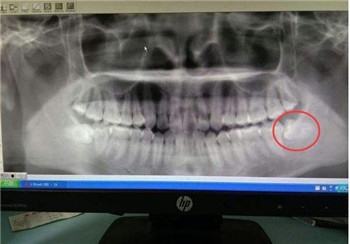

王女士怀孕前,右下牙床就存在一颗智齿,经常发炎,但是出于“能拖一会是一会”的心理,一直到怀孕了,智齿还没拔。孕后,王女士拖着不去医院没能让身体自愈,反而让病情越来越严重。等到诊治时,王女士连呼吸都成了困难。

经诊断,王女士智齿发炎导致口腔内的细菌大量增加。用药对孩子肯定有影响,大人和孩子只能选一个,王女士最终还是引产了7个月的孩子。

发生这种情况,妈妈的确有很大责任。躲过了危险的前三个月,却败给了一颗智齿。在备孕前,妈妈们一定要注意口腔健康。